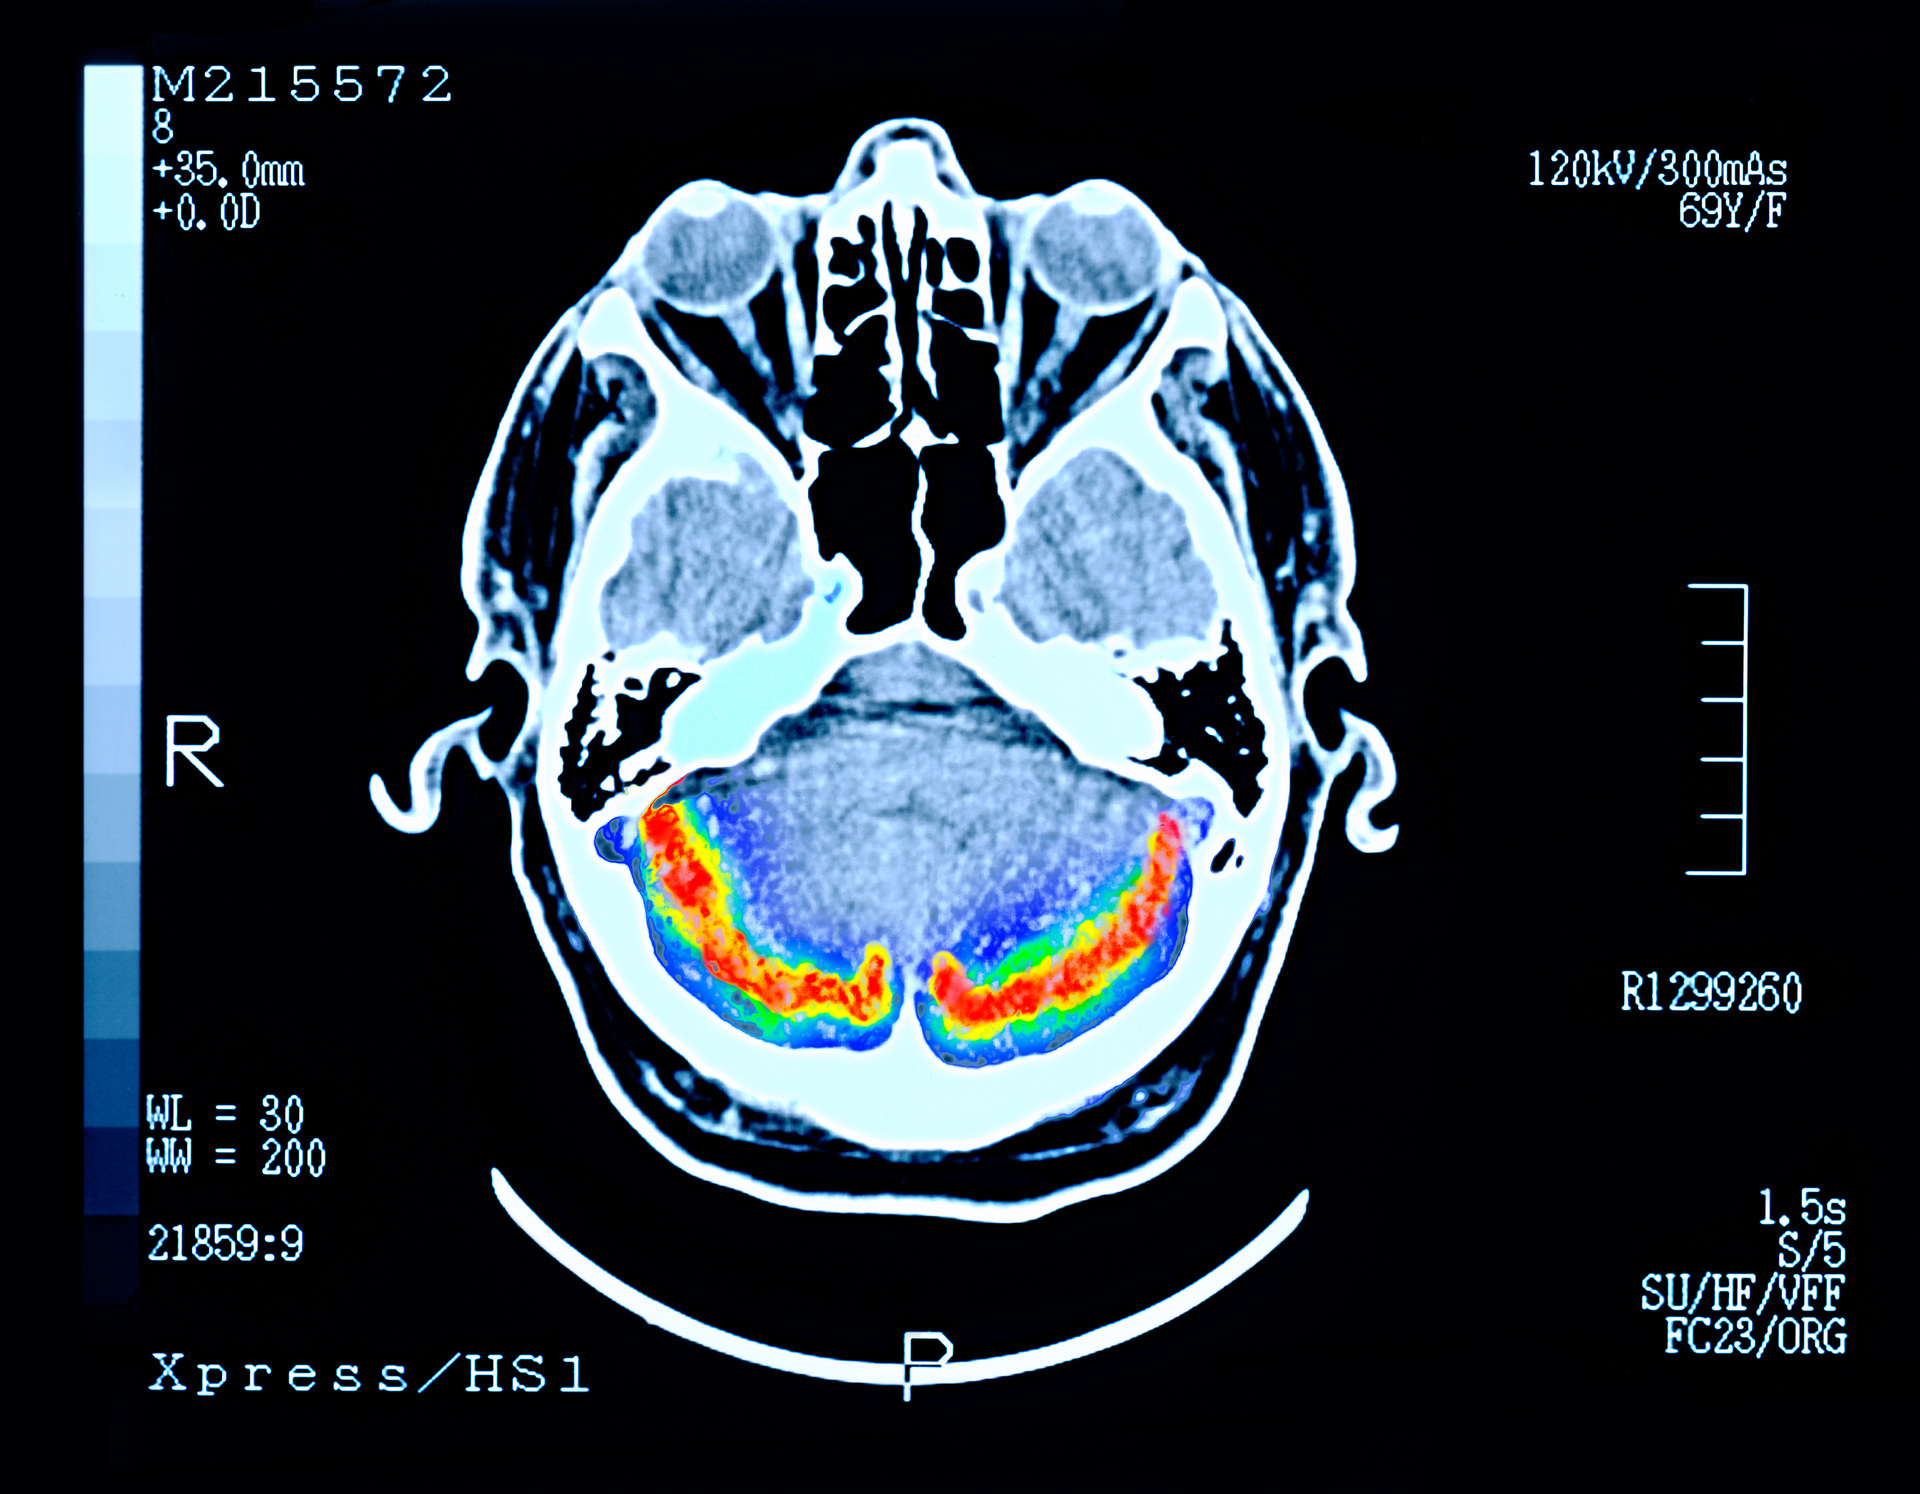

Российские учёные разработали новые химические соединения, способные остановить на ранних стадиях развитие болезни Альцгеймера, которая приводит к деменции. Вещество создано на основе уже известного препарата такрина. Прежде его назначали людям с болезнью Альцгеймера, но со временем выяснилось, что лекарство серьёзно повреждает печень пациентов. Авторам новой работы удалось модифицировать вещество так, что оно сохранило лекарственные свойства, но при этом перестало быть токсичным. Полученные учёными препараты проходят сейчас стадию доклинических испытаний.

Российские учёные из Института органического синтеза Уральского отделения РАН, Института исследования физиологически активных веществ РАН и УрФУ разработали новые химические соединения для лечения болезни Альцгеймера. По мнению авторов, в перспективе препараты на основе полученных веществ смогут останавливать развитие деменции без серьёзных побочных эффектов. Это будет возможно после проведения успешных клинических исследований на людях, сейчас разработка проходит доклинические испытания. Об этом RT сообщили в пресс-службе Минобрнауки России. Результаты исследования опубликованы в журнале Molecular Sciences.

Кроме того, новые химические соединения могут останавливать процесс образования в мозгу скоплений особых бета-амилоидных белков, которые приводят к отмиранию нейронов при деменции, считают авторы исследования.

«Точные причины развития болезни Альцгеймера до сих пор не до конца понятны. У этой болезни есть генетический компонент, поэтому полностью её излечить пока не получится. Однако в связи с улучшением методов диагностики можно распознать болезнь в самом начале. Если начать приём препарата как можно раньше, можно увеличить количество ацетилхолина, отодвинуть на много лет образование крупных агрегатов (бляшек. — RT) бета-амилоида в нейронах и защитить сами нейроны от окислительного стресса. Тогда сохранятся когнитивные процессы и человек сможет ещё долго продолжать свою деятельность», — добавила Мария Улитко.